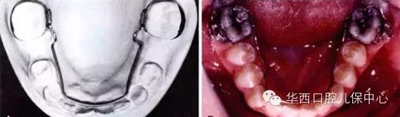

圖示:乳尖牙至乳磨牙的寬度大于繼承恒牙的寬度

剩余的間隙稱為替牙間隙(leeway space)

圖為幾種活動擴(kuò)弓矯治器的設(shè)計